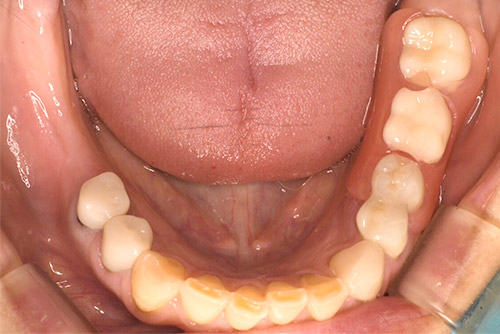

ノンクラスプデンチャー:40代 女性

治療前

治療後

| 治療名 | ノンクラスプデンチャー |

|---|---|

| 患者情報 | 40代 女性 |

| 執刀医 | 大塚院長 |

| 治療内容 | 左下欠損部を光学印象のカメラで撮影する事により型取りを行わないでノンクラスプの義歯を作製。 |

| 治療期間 | 2回(15分) |

| 費用(税込) | 330,000円 |

| 治療に対するリスク | 経年的な歯肉の変化で適合が緩くなる場合があります。 |